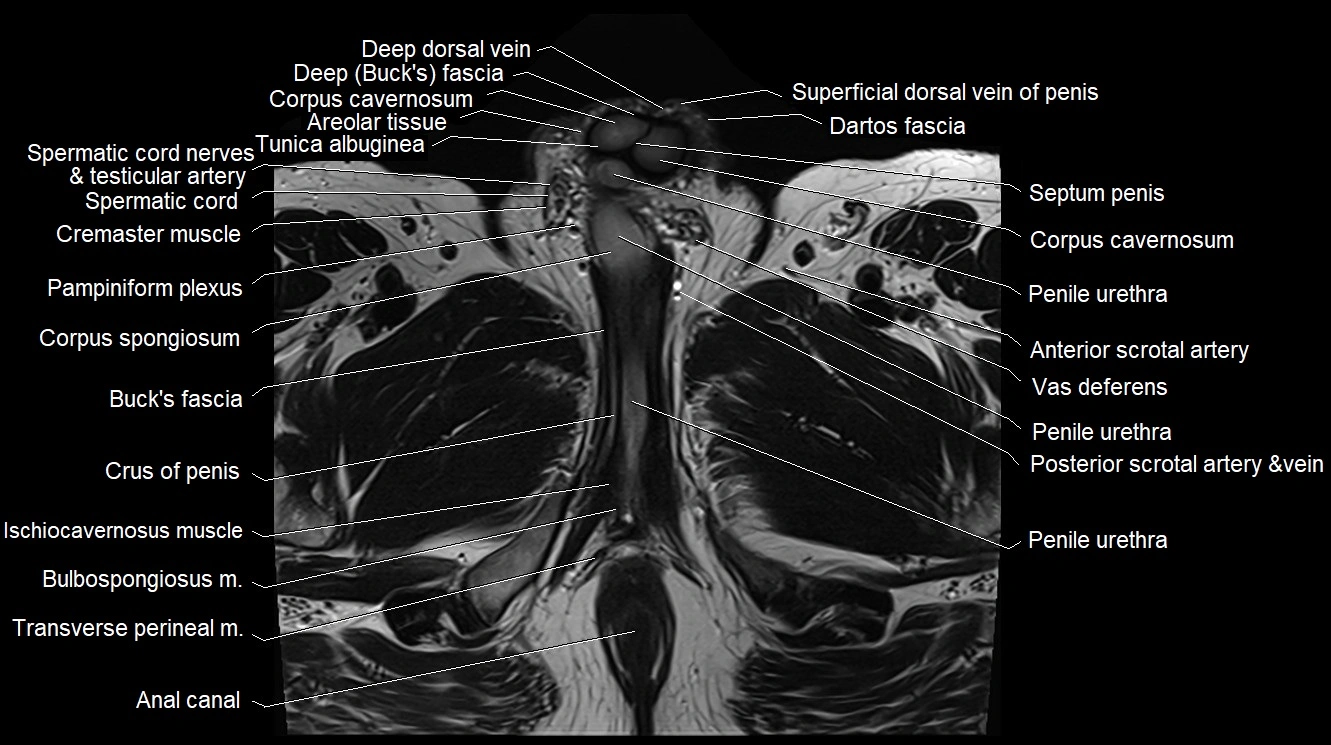

MRI image